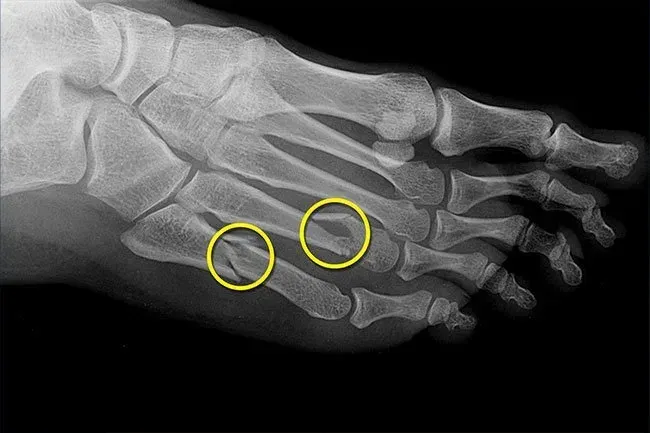

Fractures de stress

Pour les femmes, les changements hormonaux qui accompagnent la ménopause peuvent réduire votre densité osseuse (ostéoporose) et faciliter la fracture des os, y compris ceux de vos pieds. Les hommes peuvent également obtenir plus d'os cassants à mesure qu'ils vieillissent. Une fracture de stress a besoin de plusieurs semaines de repos pour guérir. Vous voudrez renforcer vos os avec un régime d'exercice et peut-être aussi des médicaments. Demandez à votre médecin les prestations des risques et ce qui vous aiderait le plus.